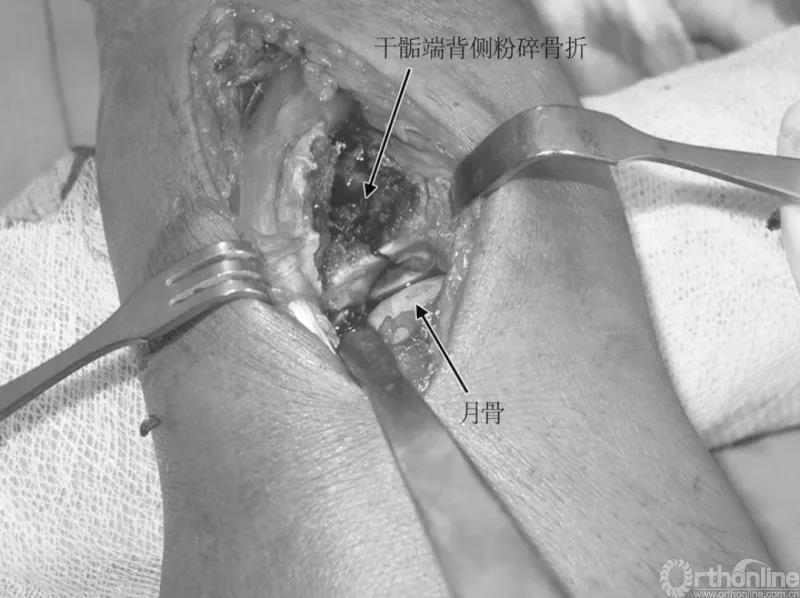

图6 术中见关节面

另做一切口进入第二伸肌间室,在直视下复位侧柱。从桡骨茎突上松解肱桡肌腱有助于内固定的植入,并可缓和茎突上肌肉的变形力。背侧入路显露过程中唯一有损伤风险的血管神经结构是桡神经浅支,在第二间室切开时应注意探查并保护。以月骨、舟骨为参照物,直视下复位关节面,并在尽可能的远端、软骨下骨打入1mm克氏针做临时固定。

上述过程中,每一步均需影像学指导。克氏针也可作为钢板远端放置的标志。侧柱首先复位,之后是背侧柱。从大骨块向小骨块逐步拼接是解决复位的最佳顺序。干骺端区域剩下的孔隙,如有需要可用自体骨或人工替代物进行填充。如此,可进一步加强结构的稳定性。然后放置选取好的钢板,在靠近骨折线处打入一枚非锁定皮质螺钉,将钢板固定在骨折近端。